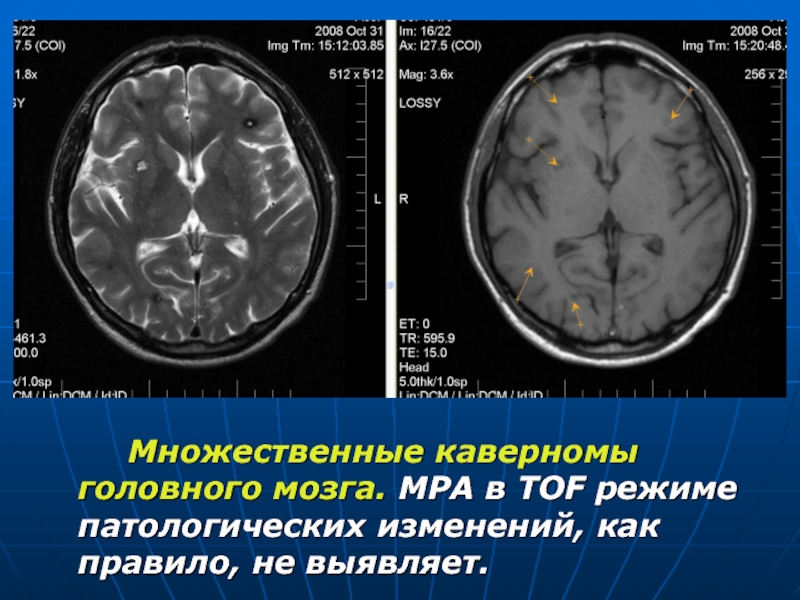

Мр картина венозной ангиомы левой гемисферы мозжечка - 96 фото